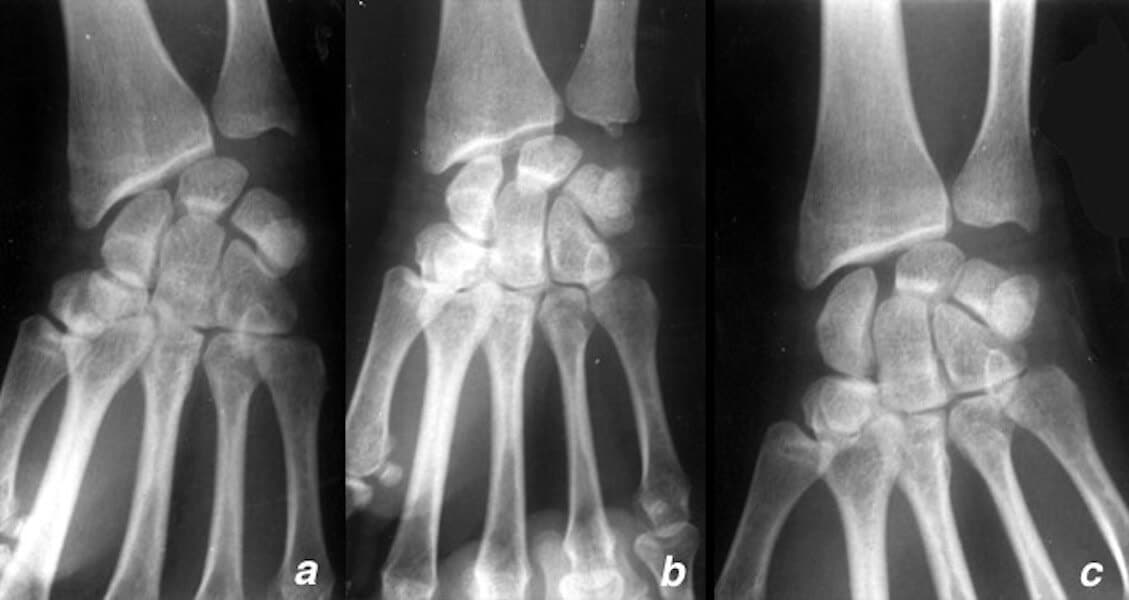

entorse ligament poignet rupture

Diastasis important par rupture ligamentaire complète du ligament scapho lunaire

D’autres lésions intracarpiennes existent, notamment la rupture du ligament luno-triquétral. Son pronostic est généralement moins grave et nécessite moins souvent une chirurgie. Tous les ligaments du carpe peuvent être touchés. Toutefois, les lésions des ligaments autres que scapho-lunaire et luno-triquétral sont souvent moins préoccupantes.